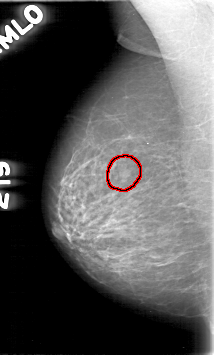

D_4068_1.RIGHT_MLO

FILE: D_4068_1.RIGHT_MLO.OVERLAY

TOTAL_ABNORMALITIES 1

ABNORMALITY 1

LESION_TYPE MASS SHAPE IRREGULAR MARGINS OBSCURED

ASSESSMENT 0

SUBTLETY 4

PATHOLOGY BENIGN

TOTAL_OUTLINES 1

BOUNDARY